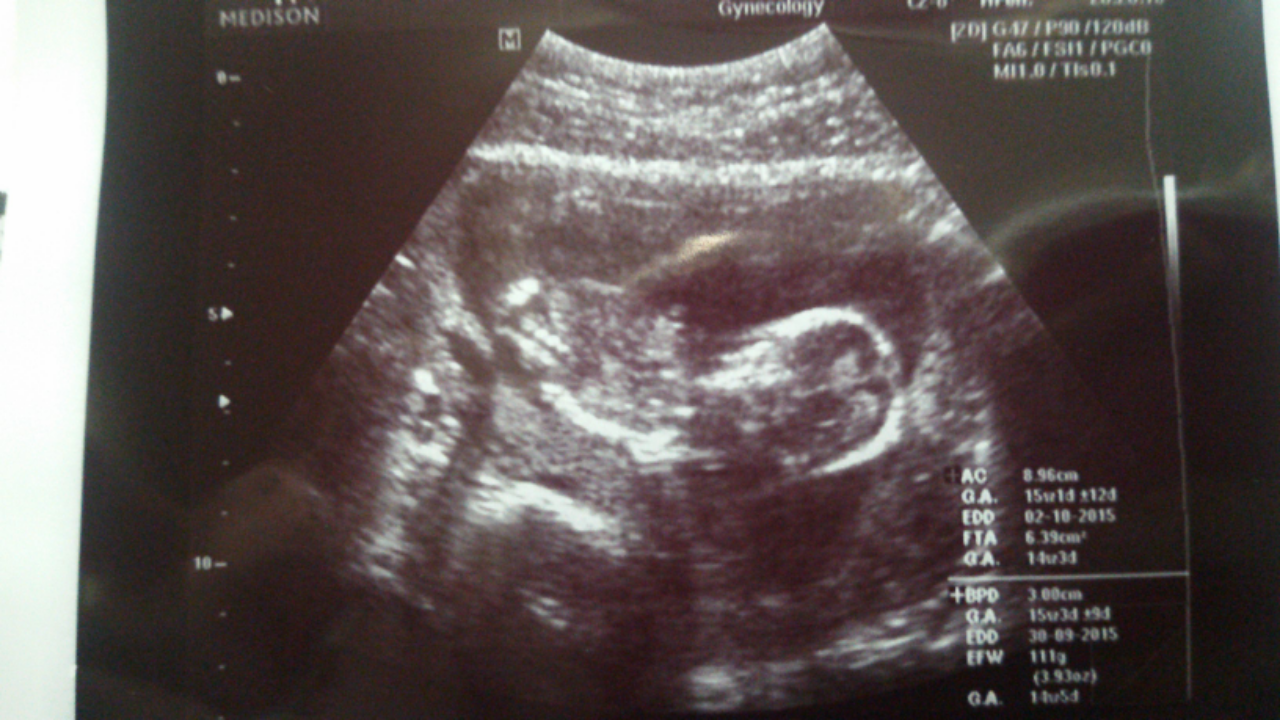

14 weeks, 1 day. I had an abdominal u/s. I've decided to call it my little wiggle worm because it wouldn't stop moving around, and stretching! It took three tries for the tech to capture the heartbeat (148). At one point she managed to get positioned just right to see it's entire front, and not even a second later, it completely turned itself around